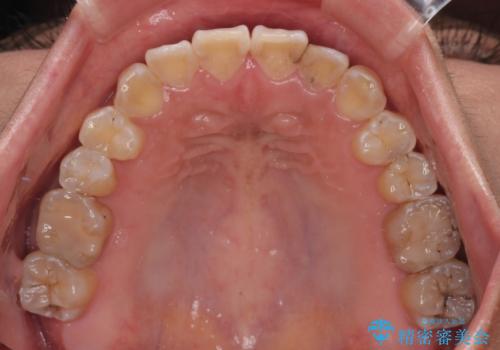

- 上下の前歯のでこぼこを気にして来院された患者様です。

途中転勤や出産があり、通院できない期間が長くありましたが、無事に歯列を整えることができました。